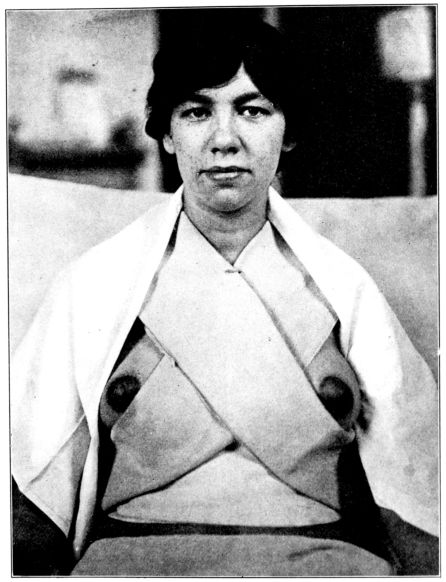

| 125. | Y binder applied | 346 |

| 126. | The same seen from the other side | 347 |

| 127. | Indian binder | 347 |